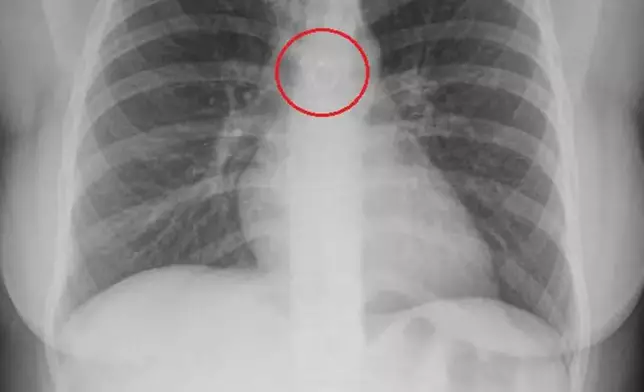

綜合外媒報導,墨西哥一名26歲女子巴拉哈斯(Monica Deyanira Cabrera Barajas)早前因持續咳嗽逾1個月未見好轉,遂前往醫院檢查。原以為只是普通小病,結果經X光檢查後發現,她的鼻環竟卡入肺部位置,甚至距離主動脈僅約0.5毫米,險些造成致命後果。

醫生透過影像檢查發現,巴拉哈斯的肺部內竟有一枚金屬鼻環,且緊貼主動脈,若位置稍有變動,隨時可能刺穿肺部或血管,引發氣胸或大量出血死亡。巴拉哈斯事後於TikTok分享自身經歷表示,起初並未察覺鼻環遺失,更未想到會被「吸入體內」,推測或因睡眠期間不慎令鼻環脫落並誤吸入呼吸道,最終進入肺部。